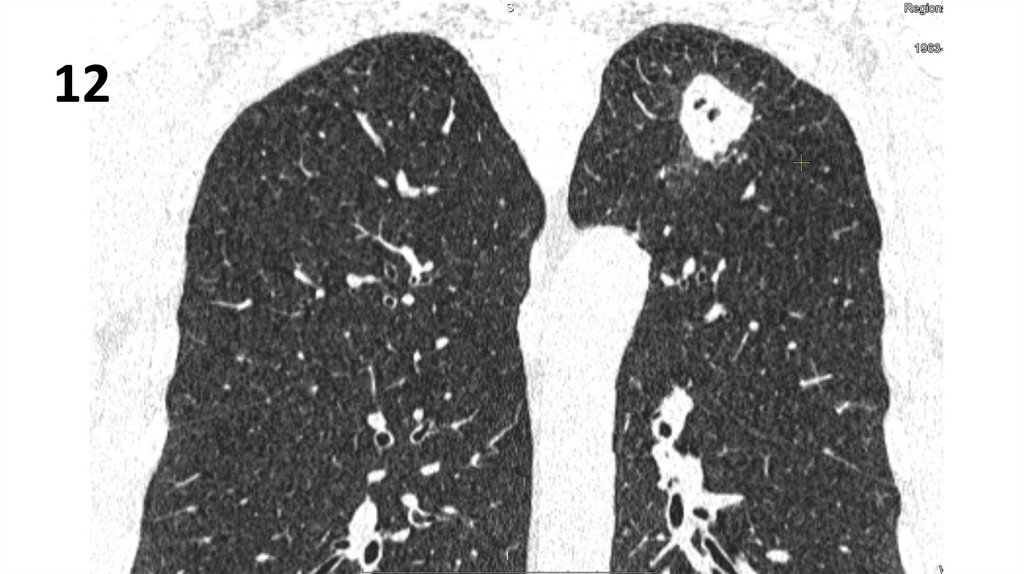

13.

12